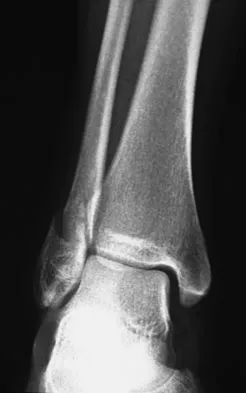

Figures 4a through 4c show the radiographs of a 43-year-old woman who sustained a twisting injury to her right ankle. She has ankle pain and tenderness medially and laterally. To help determine the optimal treatment, an external rotation stress radiograph of the ankle is obtained. This test is designed to evaluate the integrity of what structure?

Explanation

In the presence of a supination external rotation-type fracture of the distal fibula (Weber type B), stability of the ankle is best assessed by performing an external rotation stress AP view of the ankle. This test is used to assess the integrity of the deltoid ligament. The presence of a deltoid ligament rupture results in instability and generally is best managed surgically. The gravity stress test can also be used. Egol KA, Amirtharajah M, Tejwani NC, et al: Ankle stress test for predicting the need for surgical fixation of isolated fibular fractures. J Bone Joint Surg Am 2004;86:2393-2398. McConnell T, Creevy W, Tornetta P III: Stress examination of supination external rotation-type fibular fractures. J Bone Joint Surg Am 2004;86:2171-2178.